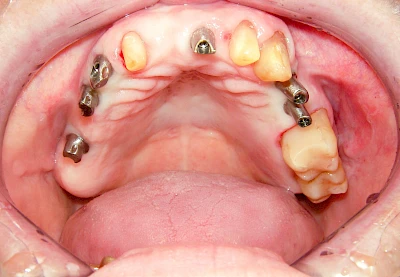

Implantate: Prothesen

Bei herausnehmbaren Prothesen werden Implantate eingesetzt, um den Halt und den Tragekomfort der Prothesen zu verbessern. Dazu kommen verschiedene Verbindungselemente zum Einsatz:

- Teleskope

- Kugelköpfe

- Tellerförmige Lokatoren

- Stege

- Magnete (selten)

Neben rein implantat-getragenen zahnärztlichen Versorgungen werden bei herausnehmbaren Prothesen Implantate auch in Sinne einer "strategischen Pfeilervermehrung" ergänzend zu eigenen Zähnen zur Verankerung eines Zahnersatzes genutzt.

Varianten zur Verankerung von abnehmbarem Zahnersatz auf Implantaten